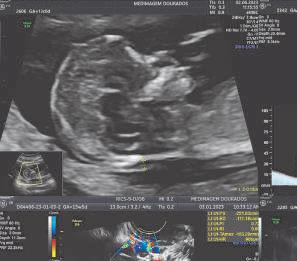

Com a gravidez confirmada, o pré-natal é realizado em consultas, onde além da avaliação clínica, o obstetra solicita exames para avaliar as condições da mãe e fazer a triagem de algumas doenças, para o melhor manejo da gestação. Os exames de imagem, cujo principal representante é a ULTRASSONOGRAFIA, fornecem imagens de órgãos e estruturas relacionadas ao ciclo gravídico, sem quaisquer efeitos adversos a mãe e ao bebê.

1 - Exame ecográfico inicial - realizado em período próximo a 8ª semana de atraso menstrual, via endovaginal, afim de confirmar se os eventos iniciais de formação ocorreram dentro dos padrões esperados (número de fetos, idade gestacional, batimento cardíaco fetal, posição da placenta, etc.).

2 - Exame morfológico do 1º trimestre / obstétrico com translucência nucal, com Doppler materno e fetal - feito entre 11 semanas e 13 semanas e 6 dias para avaliar a morfologia do bebê, placenta, líquido amniótico e colo uterino. Existem alguns sinais (marcadores) no feto, que podem ser mais frequentes em bebês com alguma anormalidade estrutural e/ou genética, possibilitando quantificar riscos de doenças que podem acometer a mãe e o bebê (risco de doenças genéticas, risco de parto prematuro e risco de pré-eclâmpsia).

Nos casos com triagem positiva (presença do sinal) existem protocolos assistenciais específicos com uso de atividade terapêutica própria. Estas análises de riscos, em conjunto, são conhecidas como Classificação/Curva de Risco, que utilizam uma ferramenta específica, o software disponibilizado para médicos certificados/auditados pela FMF – Fetal Medicine Foundation, necessário para confiabilidade e reprodutibilidade dos números encontrados.

3 - Ultrassom morfológico do 2º trimestre com Doppler materno/fetal e avaliação do colo uterino - realizada preferencialmente entre a 20ª e 24ª semanas de gestação, onde é feita uma análise minuciosa da anatomia do feto, com inte-

resse em órgãos e sistemas próprios da vida fetal, avaliação da circulação sanguínea (do útero, feto e placenta) por meio do Doppler, além da medida do colo uterino como triagem de parto prematuro.

4 - Ultrassom obstétrico com Doppler materno e fetal - realizado a partir do segundo trimestre para acompanhamento do crescimento fetal e circulação materno fetal (vitalidade fetal).

5 - Ultrassom obstétrico 3D, 4D e 5D - feita preferencialmente no segundo/terceiro trimestre, a partir da 26ª semana de gestação, cuja tecnologia permite a formação de imagens realísticas do feto.

6 - O Perfil Biofísico Fetal – executado no segundo e terceiro trimestre, a partir da 24/26ª semana de gestação, sendo recomendado para avaliar a vitalidade (bem-estar) fetal.

7 - Procedimentos invasivos fetal guiados por ultrassom - realizados para coleta de material fetal e/ou placentário em condições de acometimento fetal (como estudo genético do feto, coleta de sangue fetal, drenagem de líquido ou coleções no feto, etc.).

A ultrassonografia mudou a assistência de todo ciclo reprodutivo, com acurácia e sensibilidade na detecção de doenças e/ou condições adversas que necessitem de intervenções terapêuticas específicas. O EXAME é operador dependente, cujos resultados estão diretamente relacionados à formação, ao conhecimento e expertise. Procure sempre realizar com o especialista habilitado.